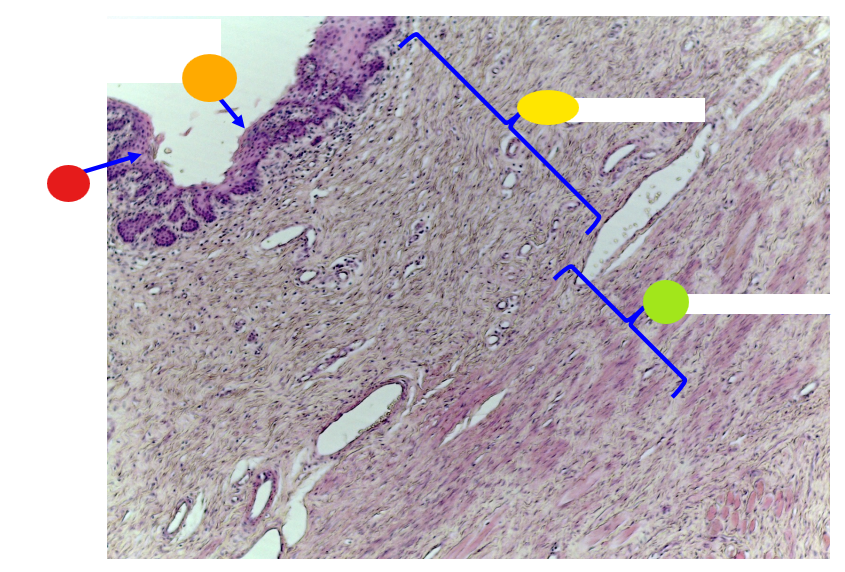

red

serosa

orange

lumen

yellow

mucosa

light green, name and tissue type

muscularis, smooth muscle

dark green

serosa

What is this?

uterine tube

red

lamina prioria

orange

simple columnar epithelium

yellow

lumen

what is this?

uterine tube

What tissue type is the epithelium/inner linning of the uterine tube?

simple columnar epithelium